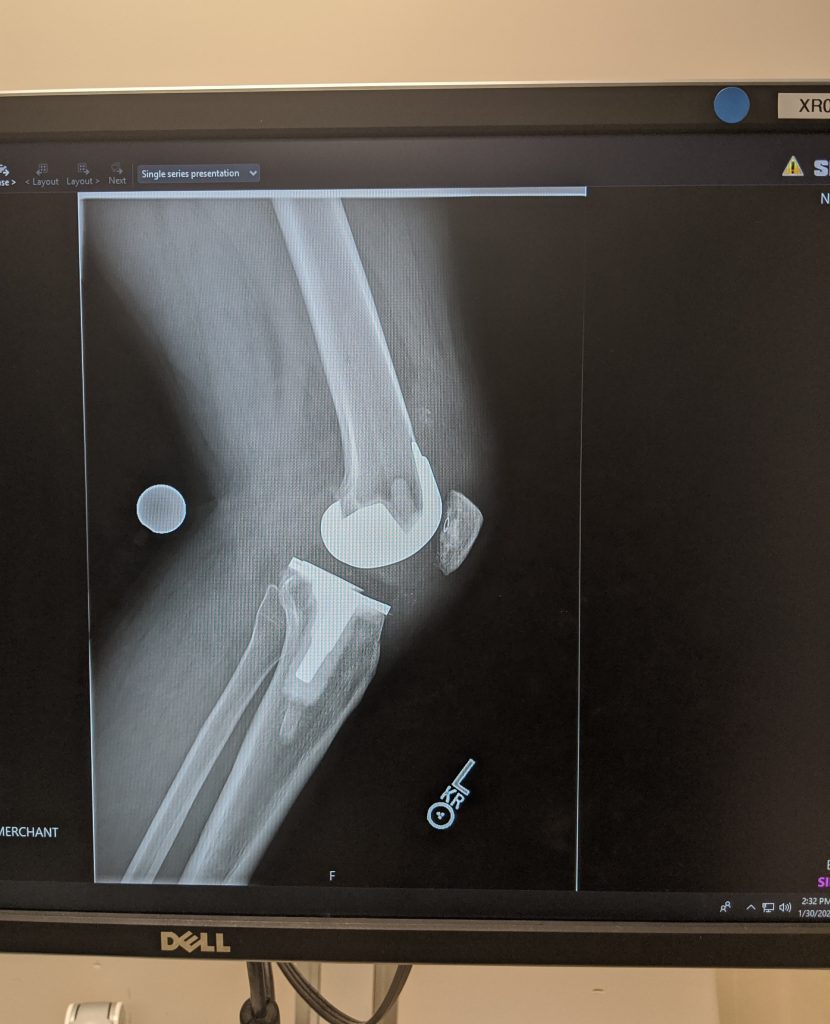

My story beings some 10 years ago when I first started to notice pain in both knees at the same time. The right was worse than that left, but as the years went by the cartilage in both knees slowly dwindled to nothing and I was bone on bone. Leaving me in extreme pain every time I would do anything regarding my knees like, walking, stairs or bike, sat & stood up, bending or running. My quality of life was getting worse and I couldn’t walk 4 blocks without stopping to rest.

The surgery took place December 18, 2019, and took about 4 hours. After 2 days PT was in my room getting me on a walker and having me walk up and down the halls. After 4 days I was trying stairs and longer walks. I stayed in the hospital for 6 days and made it home for Christmas Eve.

Thanks to Dr. Haas and his patented microscopic procedures, I no longer have any knee joint arthritic pain and after just 10 weeks, I am back to work and navigating stairs, driving, sitting & standing with no pain and no complications. I am still in PT and muscles are still recovering and there is some tenderness, but that will go away with time and I can bend my knees more than I could pre-op.